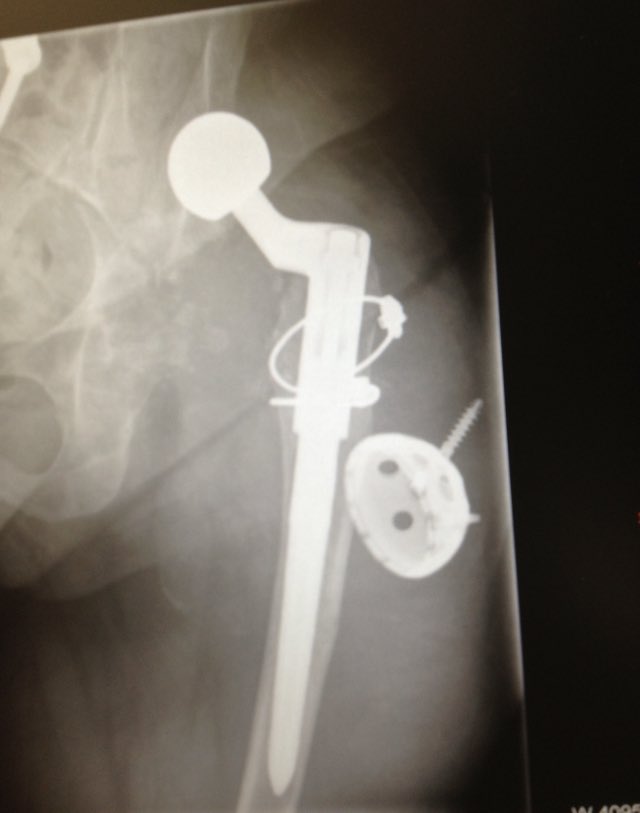

@aschwartz45 @generalorthomd Those are tm modular sockets, not continuum. Will need trilogy liners

Implant ID? Is this the Zimmer one that has NOT been recalled? Currently asymptomatic